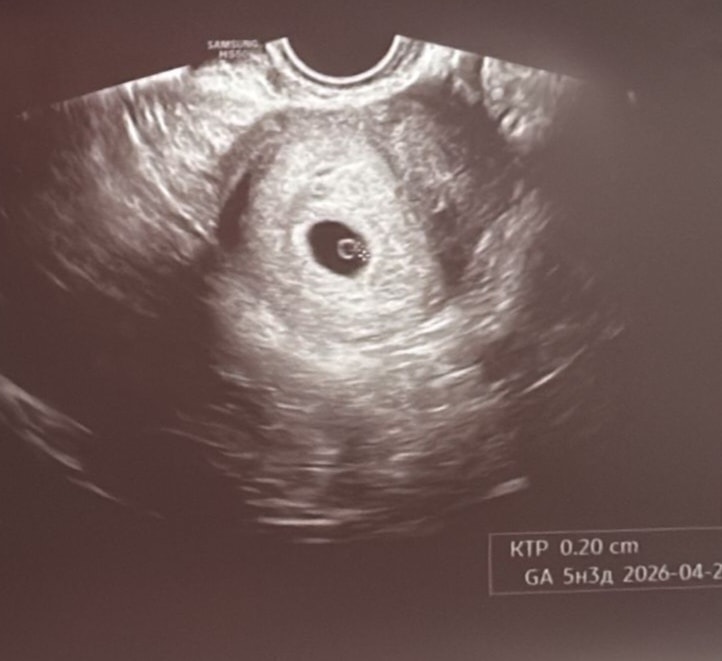

Узи на 5 неделе 3 дня. (4-5недель) эмбриональный

Здравствуйте всем, я была на своем первом узи недавно, врач определил плодное яйцо в полости матки, через 2 недели сказал приходить слушать сердечко. Я спросила, что это за точка в плодном яйце? Он сказал, что это уже будущий она или он… а я смотрю.. и почему то сомневаюсь, не рано? Точно ли это эмбрион уже виден?

Это не эмбрион, а желточный мешочек. Но то, что он появился, - хороший знак. Значит, скоро появится эмбрион.

У меня в 5,3 недели тоже видно ПЯ и ЖМ